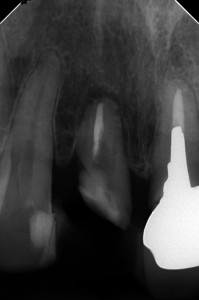

外科的廷出の2か月後

2枚目の骨とのギャップに注目

たった2か月で、ここまで骨ができるのが凄いですよね( ..)φメモメモ

外科的提出後は意外と骨の回復早いです。

根尖病巣と違うからなんでしょうね。

まだ、すこーし骨縁下欠損がありますが、・・・

手技的に矯正で引っ張るより格段に易しいので、若手の先生も是非実践されてみてはいかがでしょう。

術直後 骨の再生が認められる

骨の再生が認められる